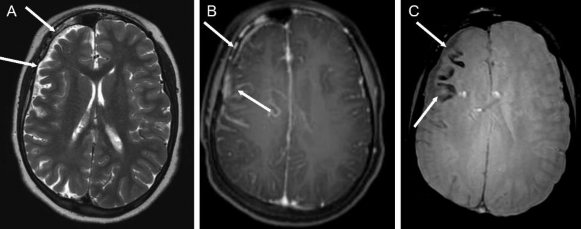

Hình 1.8. Loạn sản vỏ não khu trú hồi cạnh hải mã và hồi chẩm thái dương trái

Nguồn trích dẫn: Hiba AH, Lawrence JH. Uptodate. 2018; Topic 14040 [29].

Hình 1.9. Dị dạng u mạch thể hang tính chất gia đình